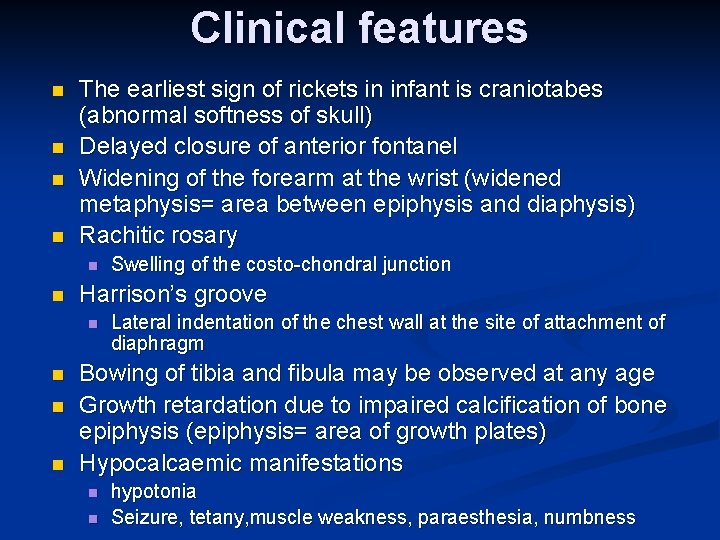

Clinical features n n The earliest sign of rickets in infant is craniotabes (abnormal softness of skull) Delayed closure of anterior fontanel Widening of the forearm at the wrist (widened metaphysis= area between epiphysis and diaphysis) Rachitic rosary n n Harrison’s groove n n Swelling of the costo-chondral junction Lateral indentation of the chest wall at the site of attachment of diaphragm Bowing of tibia and fibula may be observed at any age Growth retardation due to impaired calcification of bone epiphysis (epiphysis= area of growth plates) Hypocalcaemic manifestations n n hypotonia Seizure, tetany, muscle weakness, paraesthesia, numbness